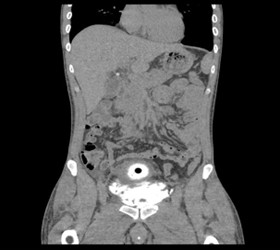

Imaging

- CECT Abdomen with Cystogram

Types of Bladder Injuries

- Extra peritoneal Bladder Injury

- Intraperitoneal Bladder Injury

Extra peritoneal Bladder Injury

Intraperitoneal Bladder Injury

Management

- Conservative management for uncomplicated extraperitonel bladder injuries

- All penetrating or intraperitoneal injuries should be managed by immediate operative repair